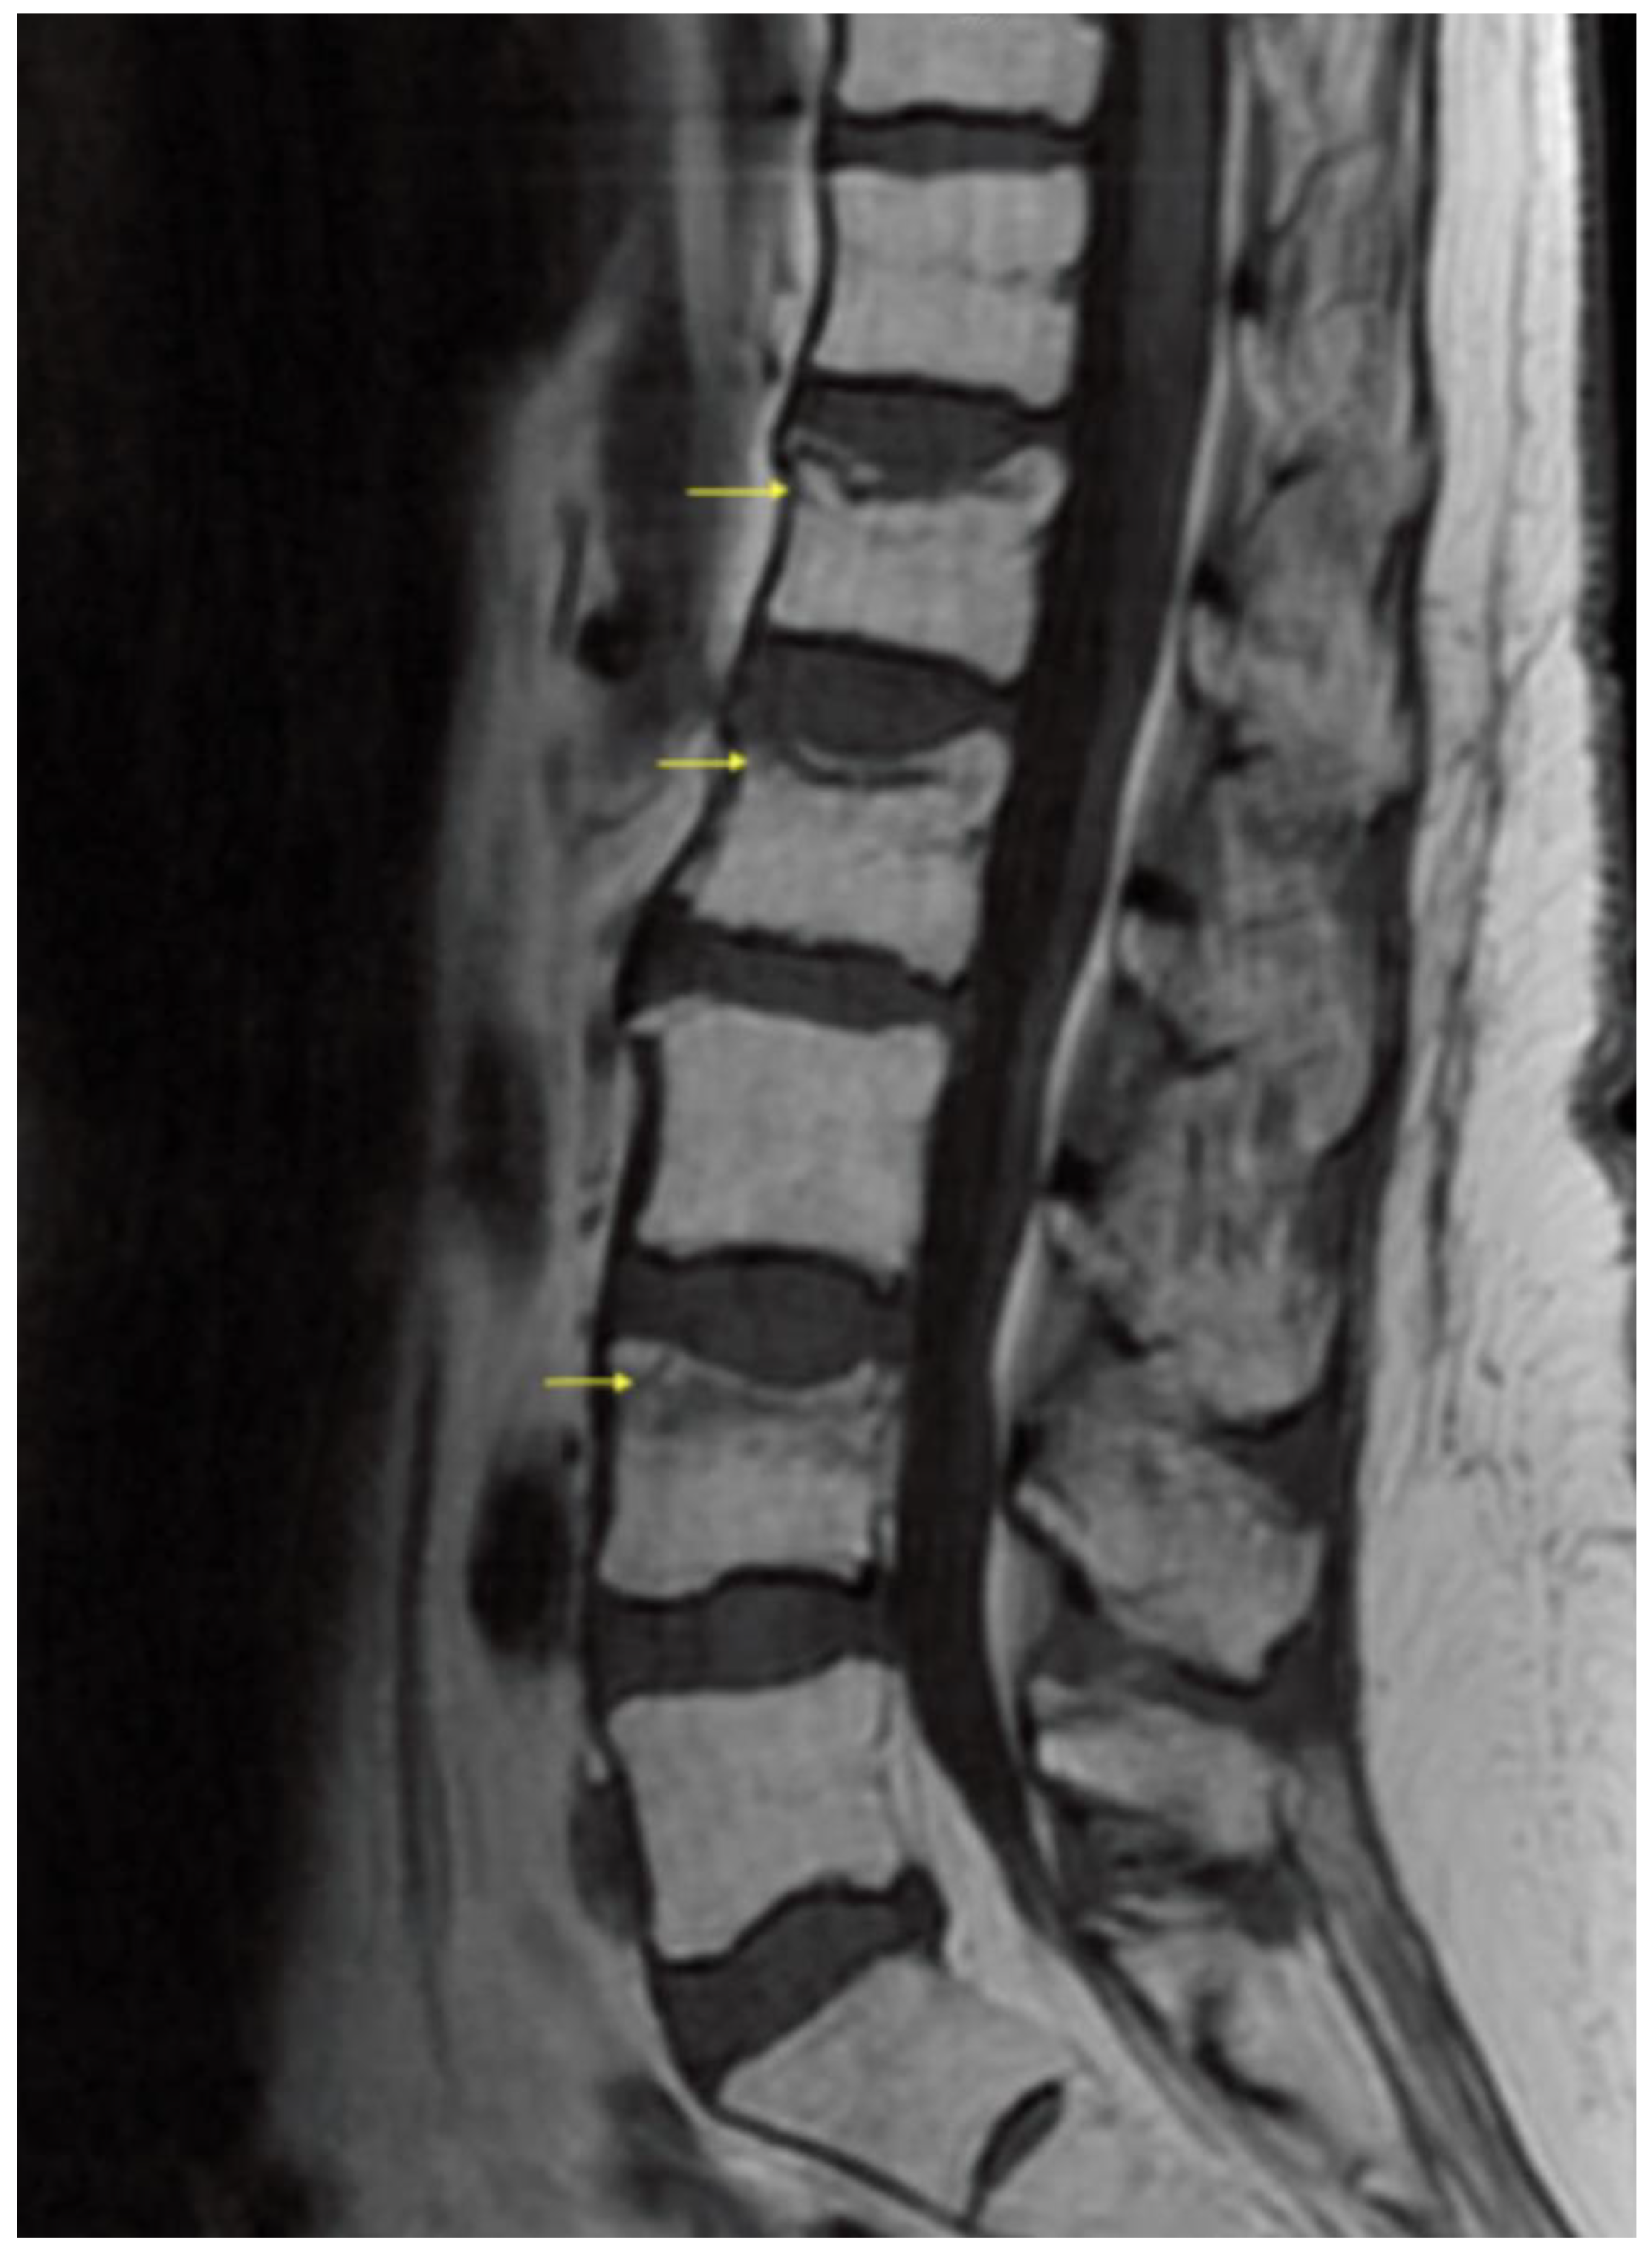

Figure and Table Surgical Treatment of Vertebral Compression Fracture

Figure and Table Surgical Treatment of Vertebral Compression Fracture Compression Fracture Definition a compression fracture is a break in a vertebra that causes it to collapse and press on the spinal cord or nerves. a compression fracture is a broken bone that causes your vertebrae to collapse, making them shorter. vertebral compression fractures (vcfs) are the most common complication of osteoporosis, affecting more than 700,000 americans. spinal compression. Compression Fracture Definition.